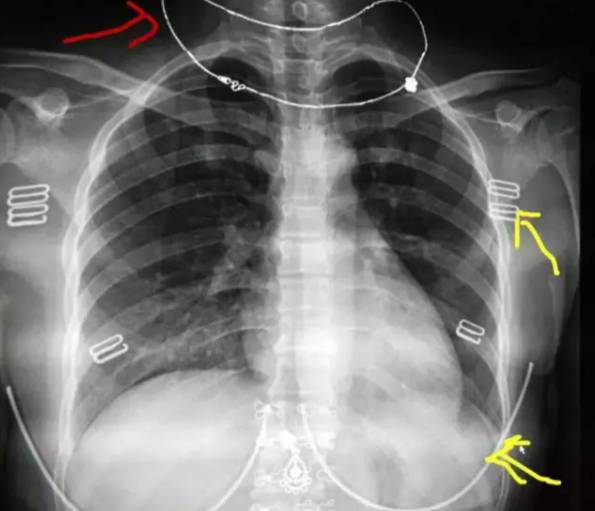

比如戴着项链拍胸部X光,项链的伪影可能刚好遮住肺部的微小病变,从而导致医生误判或漏诊。

图源:网络